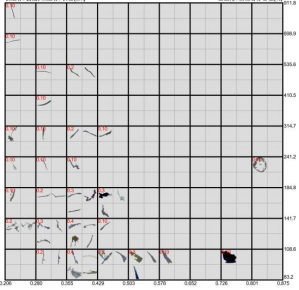

3.顯微計數:將平皿置于顯微鏡載物臺,調好入射光,以100倍或適宜倍數放大,待濾膜格柵清晰后,移動坐標軸,逐一計數有效過濾面積上最長粒徑大于規定粒徑的微粒數量。平行試驗兩份,最終結果以兩次測定的平均值為準。